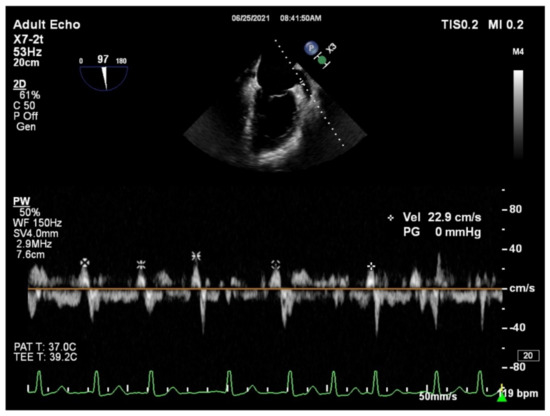

2.2. Transthoracic and Transesophageal Echocardiogram

All patients underwent both transthoracic echocardiography (TTE) and transesophageal echocardiography (TEE) within 24 h before RFCA. All the parameters were performed according to the American Society of Echocardiography guidelines. During TTE left ventricular end-systolic, and end-diastolic volumes (LVESV and LVEDV, respectively), and the left ventricular ejection fraction (LVEF) were measured. Left atrial diameter (LAD) was obtained on the parasternal long-axis view, while the left atrial volume (LAV) was calculated by the modified Simpson’s method. LAVI was obtained using body surface area correction. During TEE evaluation, LAA was visualized from the mid-oesophageal view at multiple omni-plane angles, between 45 and 100°. For pulsed-wave Doppler interrogation, the angle that provided the longest LAA dimension was used. The LAAeV was defined as a late diastolic positive outflow signal, and it was measured using a 4 mm sample volume positioned at the entry of the LAA orifice. In patients with paroxysmal AF at the time of TEE, LAAeV was described as the average value of five consecutive cardiac cycles (Figure 1). All cardiac ultrasound examinations were performed on a Philips Affiniti 50 (Philips Healthcare, Best, The Netherlands) with a 2–4 MHz microconvex transducer for ETT and a 7 MHz transducer for TEE. All echocardiographic measurements were conducted by the same two echocardiogram experts.

Figure 1. Example of measuring the left atrial appendage emptying velocity (LAAeV). The LAAeV was measured by pulsed-wave Doppler interrogation at the entry of the left atrial appendage at 84° (22.9 cm/s).